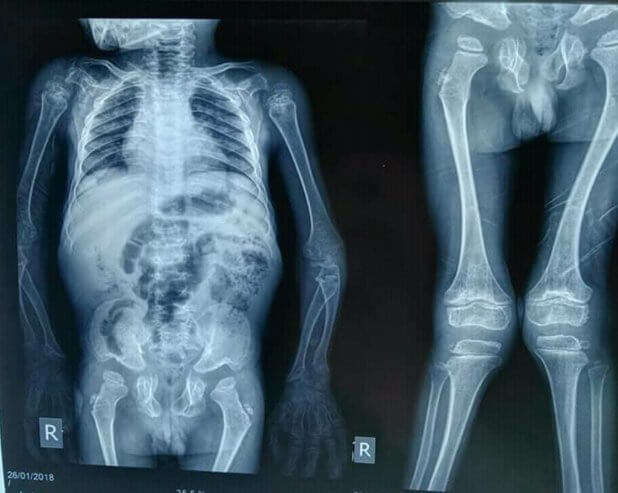

Presentan niñas y niños obesos envejecimiento prematuro